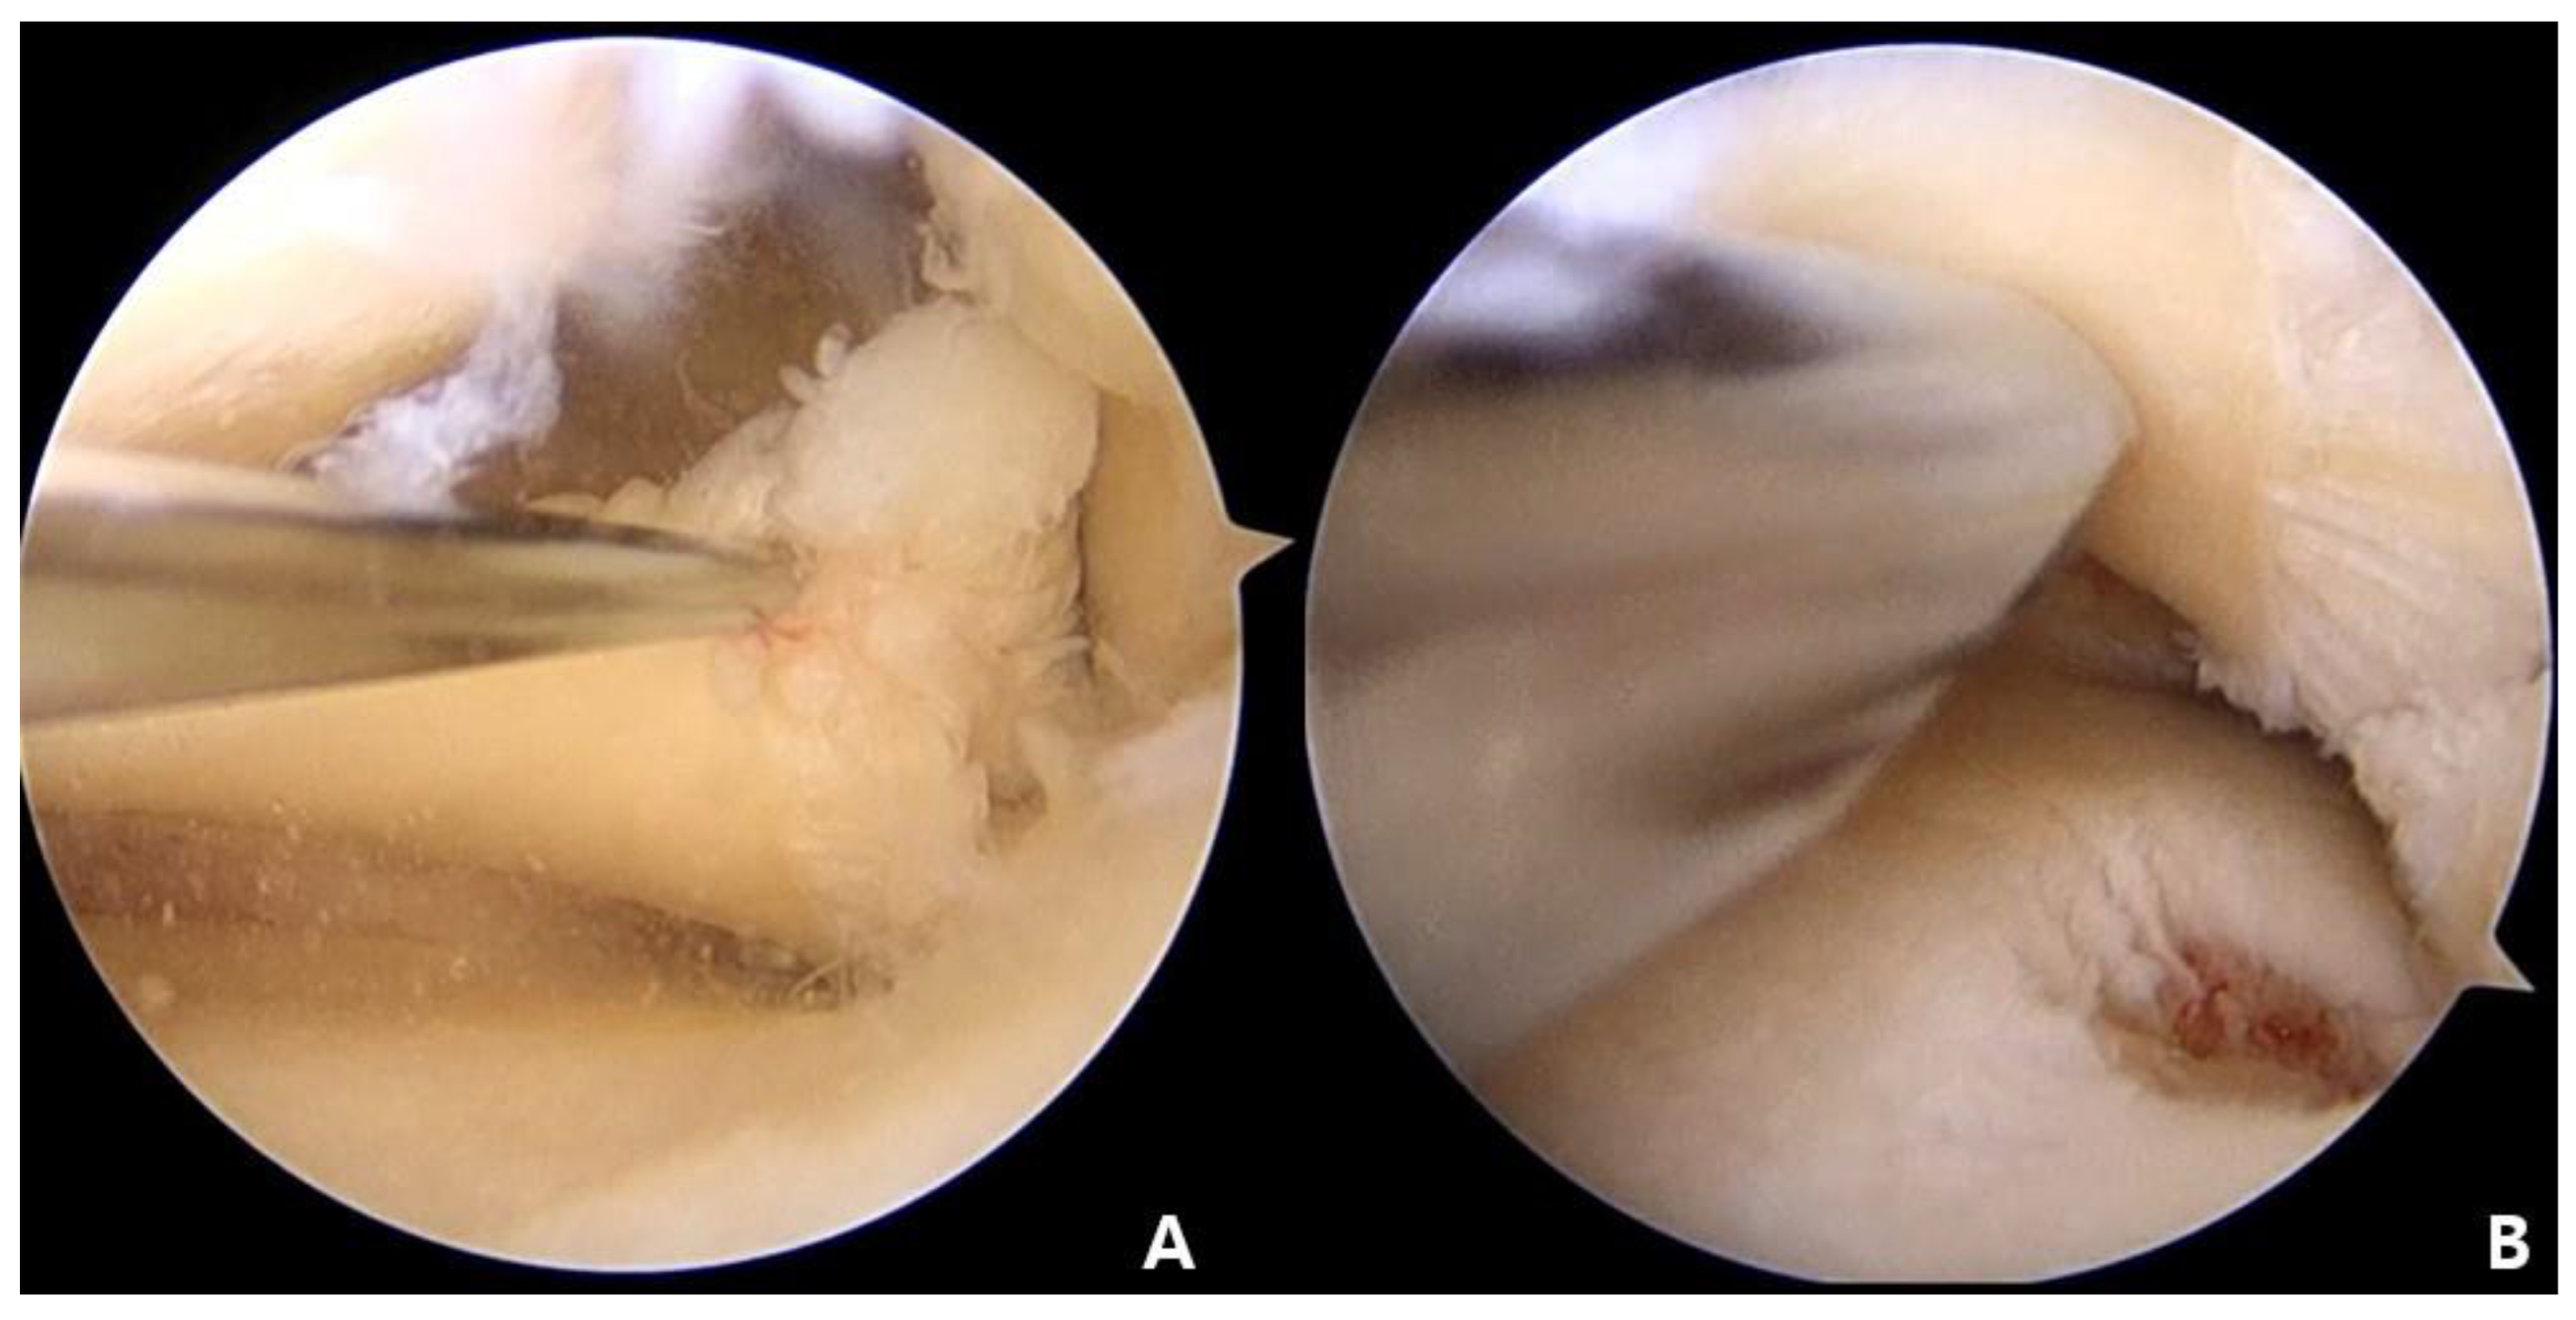

2.3. Preparation for Root Repair

An arthroscopic PassPort cannula (Arthrex, Naples, FL, USA) was inserted for the performance of a convenient procedure and to prevent twisting of the stitch. Landmarks relevant to the insertion of the MMPH, including tibial attachment of the posterior cruciate ligament, tibial medial eminence, and articular surface of the tibial plateau, were then identified. Unhealthy tissue removal of the torn meniscus edge was conducted using an arthroscopic shaver (ConMed Linvatec, Largo, FL, USA). For the creation of a bony bed, a curette was inserted through the AM portal, and bony preparation was performed (Figure 2).

Figure 2. Arthroscopic findings: (A) arthroscopic view through the anterolateral portal of medial meniscus posterior horn in left knee; (B) bone bed decortication at the attachment site of the medial meniscus.